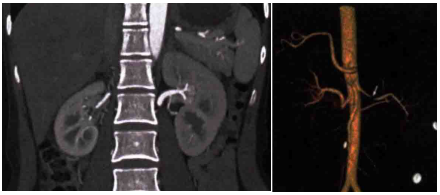

肾CTA(图1):右肾体积缩小;血管重建显示右肾动脉狭窄。肠系膜上动脉与腹主动脉夹角无明显减小,左肾静脉轻度受压。肾图:双肾有效肾血浆流量90.61 ml/min,其中左肾60.62 ml/min,右肾29.99 ml/min。

图1. 肾CTA